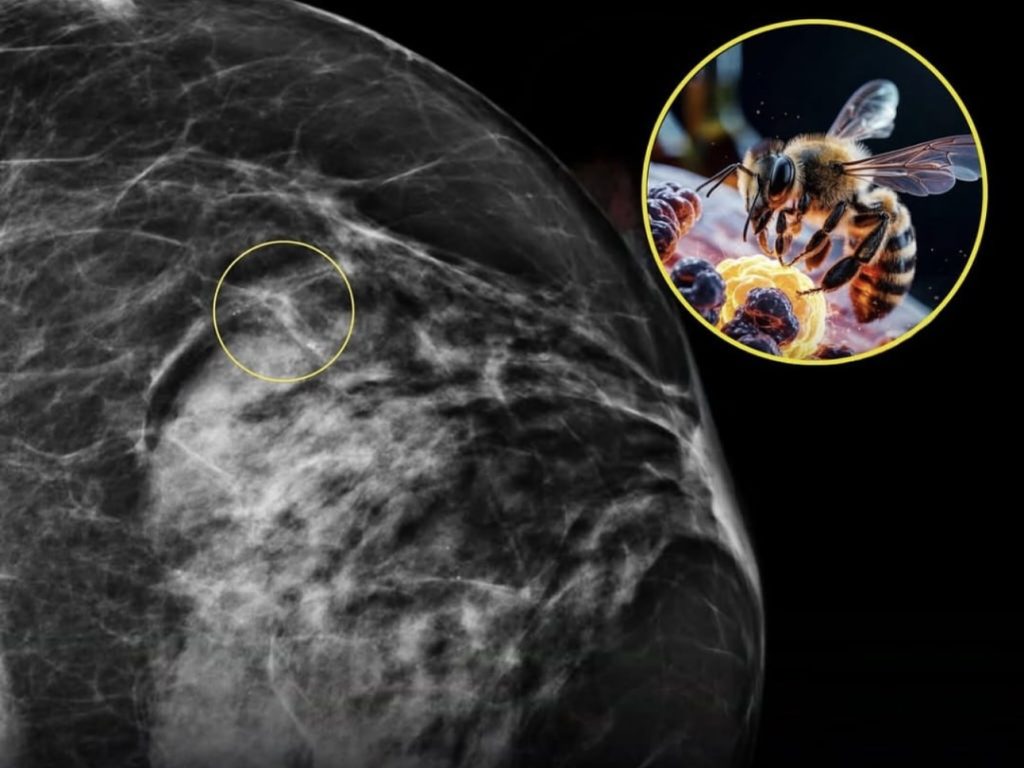

Pesquisadores do Harry Perkins Institute of Medical Research, na Austrália, descobriram que o veneno de abelha pode eliminar 100% das células de câncer de mama agressivo em testes laboratoriais de menos de 60 minutos.

O efeito é atribuído à melitina, uma molécula natural presente no veneno, que atua diretamente na membrana das células tumorais, sem prejudicar células saudáveis.